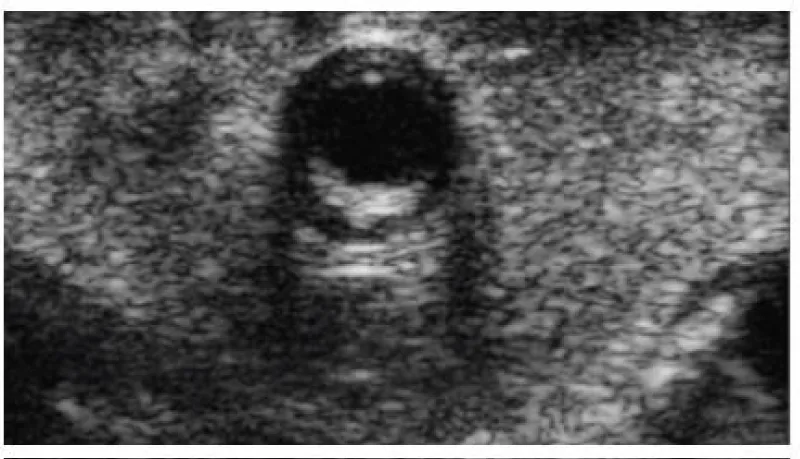

Figure 6: Anterior descending coronary artery with 2,4mm diameter and an intact arterial wall.

Download Image